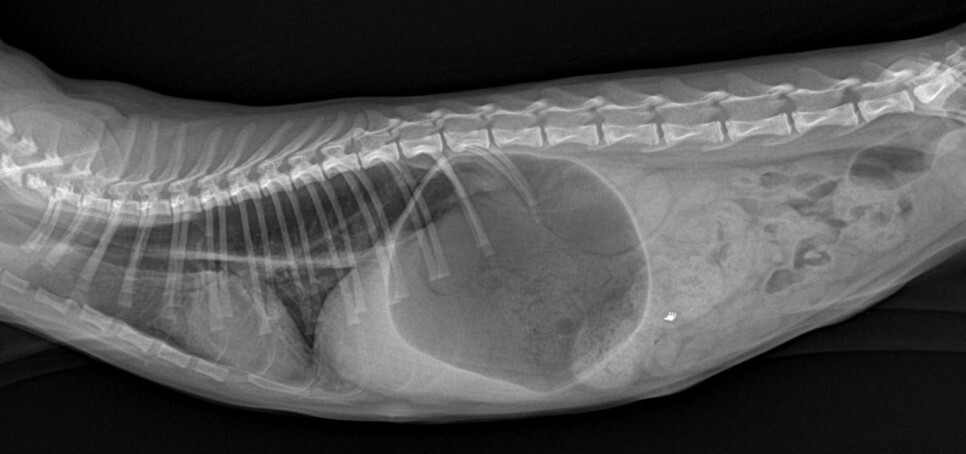

내시경 검사에서는 확장된 식도와

위-식도 연접 부위의 염증,

닫혀있어야 할 위-식도 연결 부위가

열린 상태로 위점막이 식도 내로 돌출되어

있는 것이 확인되었습니다.